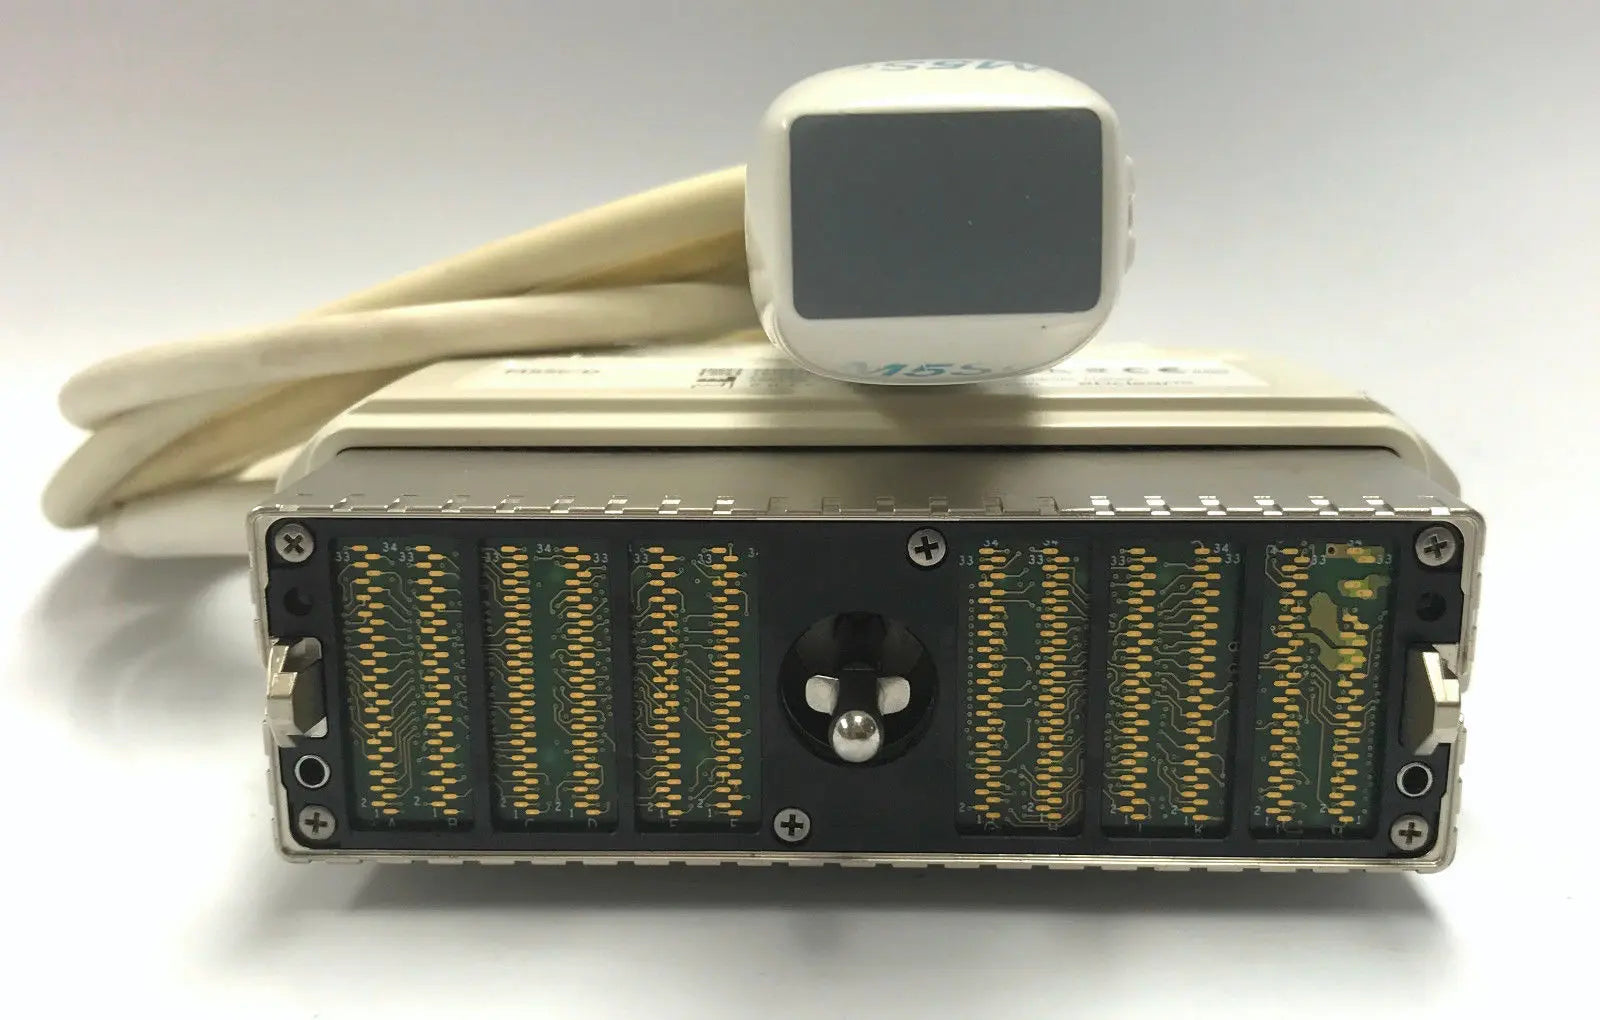

2014 GE L8-18i -RS probe for GE Ultrasound

Sale price$ 7,170.06